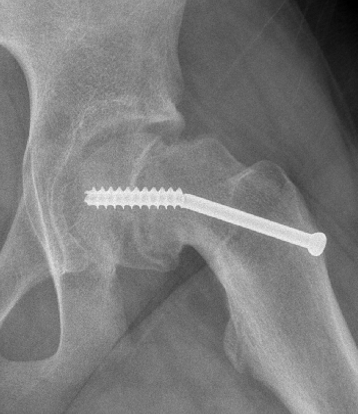

Chondrolysis

Causes

Head penetration with screw

Infection

? immune reaction